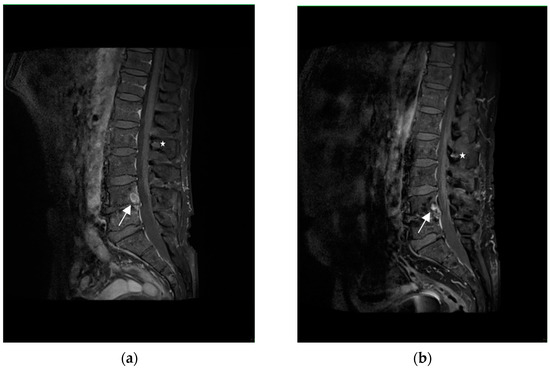

Figure 3.

T1-weighted images with fat saturation and with gadolinium contrast administration, sagittal plane. Contrast enhanced lesion in L4 vertebral body ((a)—white arrow) has reduced its size ((b)—white arrow). Similarly, the lesion in the spinous process L2 ((a)—white asterisk) has decreased in size ((b)—white asterisk).